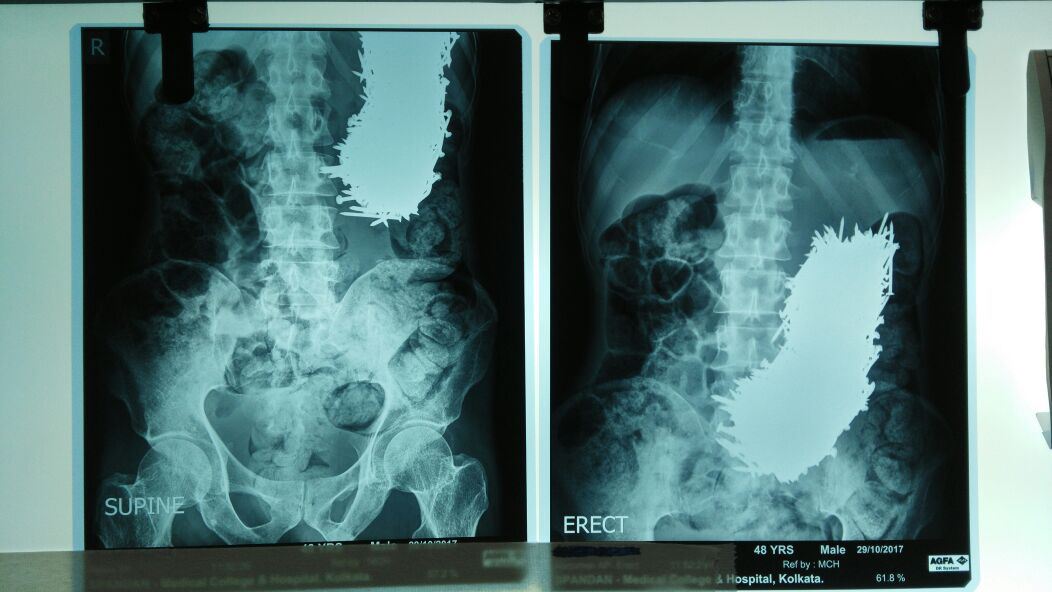

2 bulan yang lalu, lelaki dari India yang berusia 48 tahun ini, mengadu sakit pada bahagian perut. Beliau seterusnya dikejarkan ke wad kecemasan dan doktor menjalankan pengesanan ultra-bunyi.

Alangkah terkejutnya doktor yang merawat Pradip Kumar Dhali apabila mereka menemui sebilangan objek keras pada bahagian perutnya, dan menjangkakan pada mulanya adalah batu karang.

Selepas diperiksa, ia adalah sebilangan paku-paku yang sudah karat!

Pradip terus dikejarkan ke bilik pembedahan di Calcutta Medical College and Hospital dan doktor terpaksa membedah sebahagian daripada perutnya dan menggunakan magnet untuk mengeluarkan paku-paku tersebut.

Selepas pembedahan, terdapat lebih 600 paku berukuran 4 sentimeter berjaya dikeluarkan daripada perut lelaki terbabit.